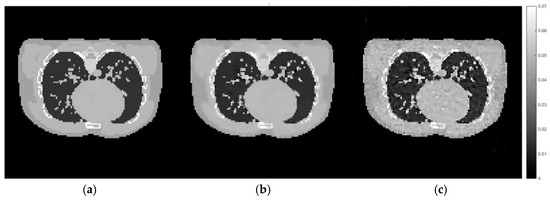

Cross-sectional slices of the reconstructed images from the female phantom using different method and hyperparameter settings. The display window is [0–0.07].

Figure 14.

Cross-sectional slices of (a) the exact image, (b) the reconstruction from the proposed method directly implemented on the female phantom data, (c) the reconstruction using the set of hyperparameters from the training dataset. The display window is [0–0.07].

According to Figure 12 and Table 5, it can be concluded that the set of hyperparameters obtained from the proposed algorithm with the training set can be applied to different imaging samples and produce a result which is superior to CGLS and TV with arbitrary parameters. However, the set of hyperparameters obtained from directly implementing the proposed algorithm with the male phantom projection shows even better results. This experiment proves that the selection of hyperparameter for the TV regularisation algorithm, specifically for the AwPCSD algorithm, is data-specific. The optimal set of hyperparameters from one training dataset can still be applied to different image sampling within a similar context. However, the optimal result might not yet be achieved. It is significant to fine-tune the hyperparameters, in order to obtain the optimal result for a given data. This is the advantage that the proposed algorithm offers, to avoid the tedious process of manual hyperparameter tuning. The same pattern of experiment is performed on the female phantom and the results, as presented in the Figure 13 and Figure 14 and Table 6, confirm the conclusion stated above.